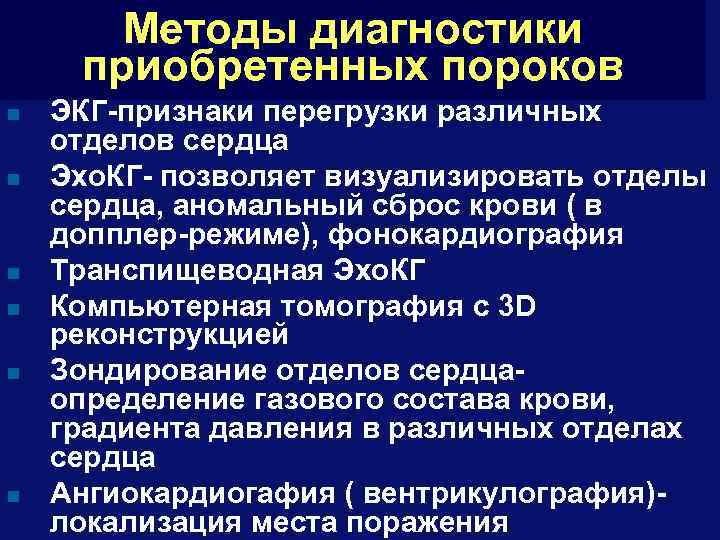

Методы диагностики приобретенных пороков n n n ЭКГ-признаки перегрузки различных отделов сердца Эхо. КГ- позволяет визуализировать отделы сердца, аномальный сброс крови ( в допплер-режиме), фонокардиография Транспищеводная Эхо. КГ Компьютерная томография с 3 D реконструкцией Зондирование отделов сердцаопределение газового состава крови, градиента давления в различных отделах сердца Ангиокардиогафия ( вентрикулография)локализация места поражения